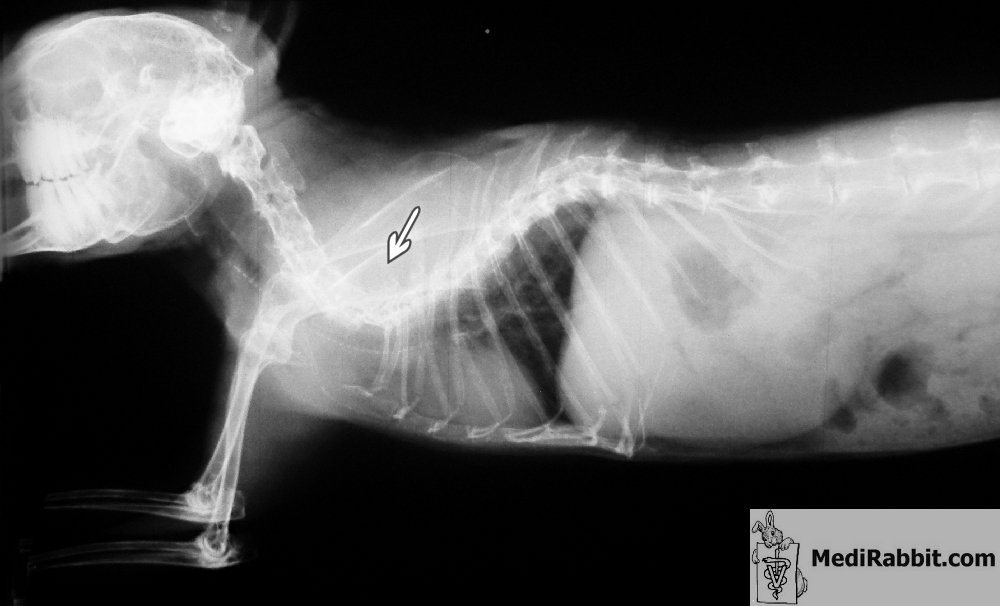

The lateral

and dorso-ventral radiographic views of Pepin

reveal a severe deformity of the spine. A rabbit with such an abnormality

often develops paresis of the lower limbs, a condition that worsens over

time. The degeneration of vertebral discs (spondyloarthropathy) contributes

to the challenging process. The rabbit will experience difficulties grooming

its fur and collecting its caecotropes.

Dr Maassen, cabinet Grodisiabois,

Liège (Belgique) Rabbit

suffering from thoracic lordosis, a deformation of the spine towards the